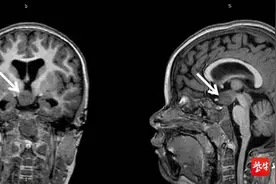

女孩身体逐渐恢复,能够下地行走,正常交流,并开始接受康复治疗。 复旦大学附属华山医院供图中新网上海3月14日电 (陈静 刘燕)一位花季女孩小虹(化名)的脑内长了巨大的畸胎瘤,压迫下丘脑和脑干这两个生命中枢。